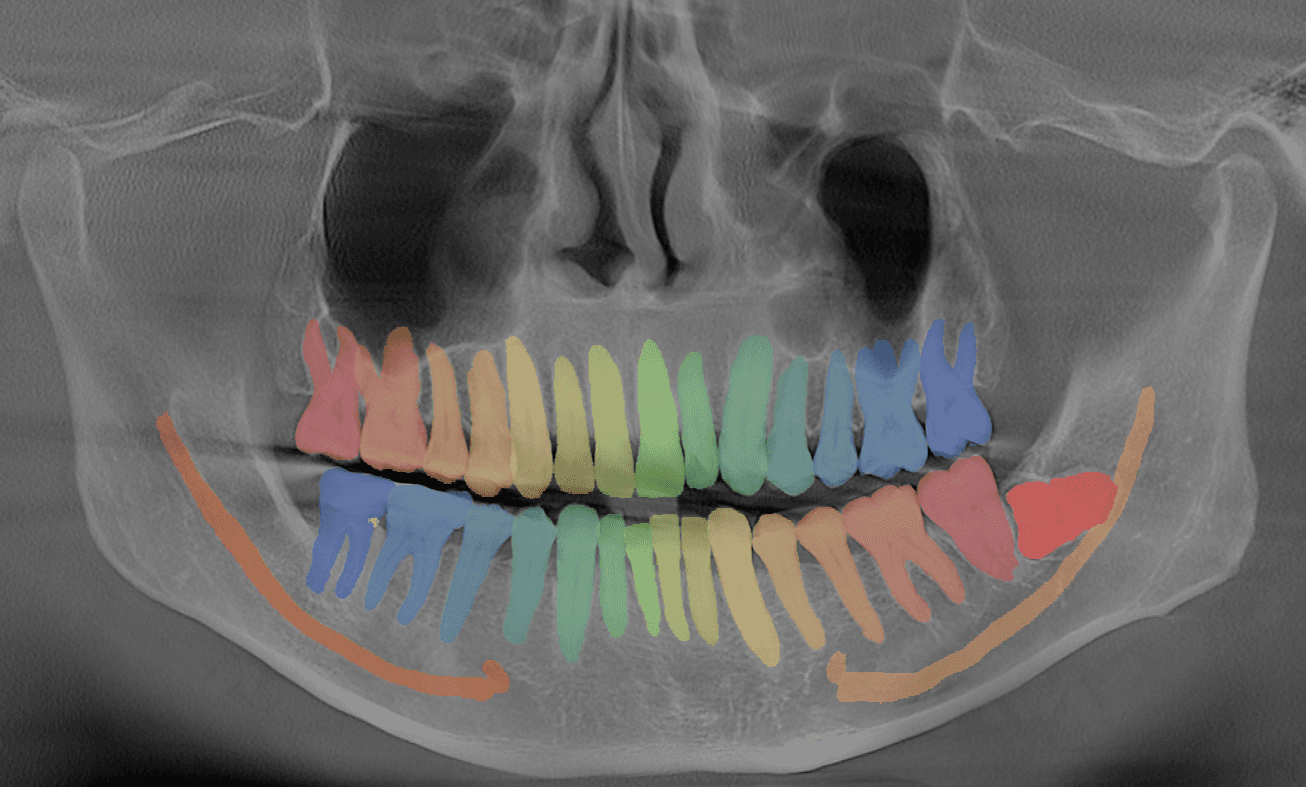

Intraoral Scan Segmentation

Automatic end-to-end segmentation of intraoral scans in seconds.

- Manual tasks are time-consuming, tedious, and expertise dependent

- Orthodontists need to segment teeth and annotate anatomical landmarks

- Our solution delivers automatic end-to-end processing in seconds